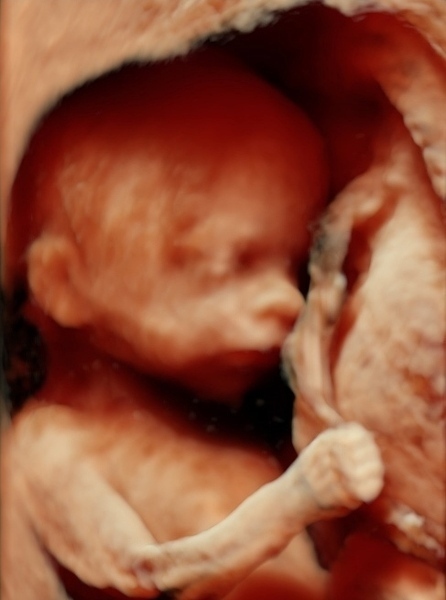

Оценка риска хромосомных патологий плода во втором триместре беременности

В связи с введением новой программы, Loote Ultraheliskriining предлагает обновлённый метод оценки риска хромосомных патологий плода во втором триместре беременности.

В данный период беременности ( с 15-й по 18-ю неделю) при помощи специальной компьютерной программы возможно оценить риск наличия хромосомных патологий у плода, взяв за основу возраст матери или результаты предварительно сделанных Double или Triple тестов.

Во время ультразвукового обследования для калькуляции риска берутся в расчёт десять различных ультразвуковых маркеров:

1. толщину шейной складки;

2. наличие носовой кости;

3. наличие аберрантной правой подключичной артерии (ARSA);

4. размещение верхней челюсти;

5. наличие отёка переносицы;

6. ширину желудочков мозга;

7. длину бедренной кости;

8. длину плечевой кости;

9. ультразвуковую эхогенность кишечника;

10. ширину почечных лоханок.